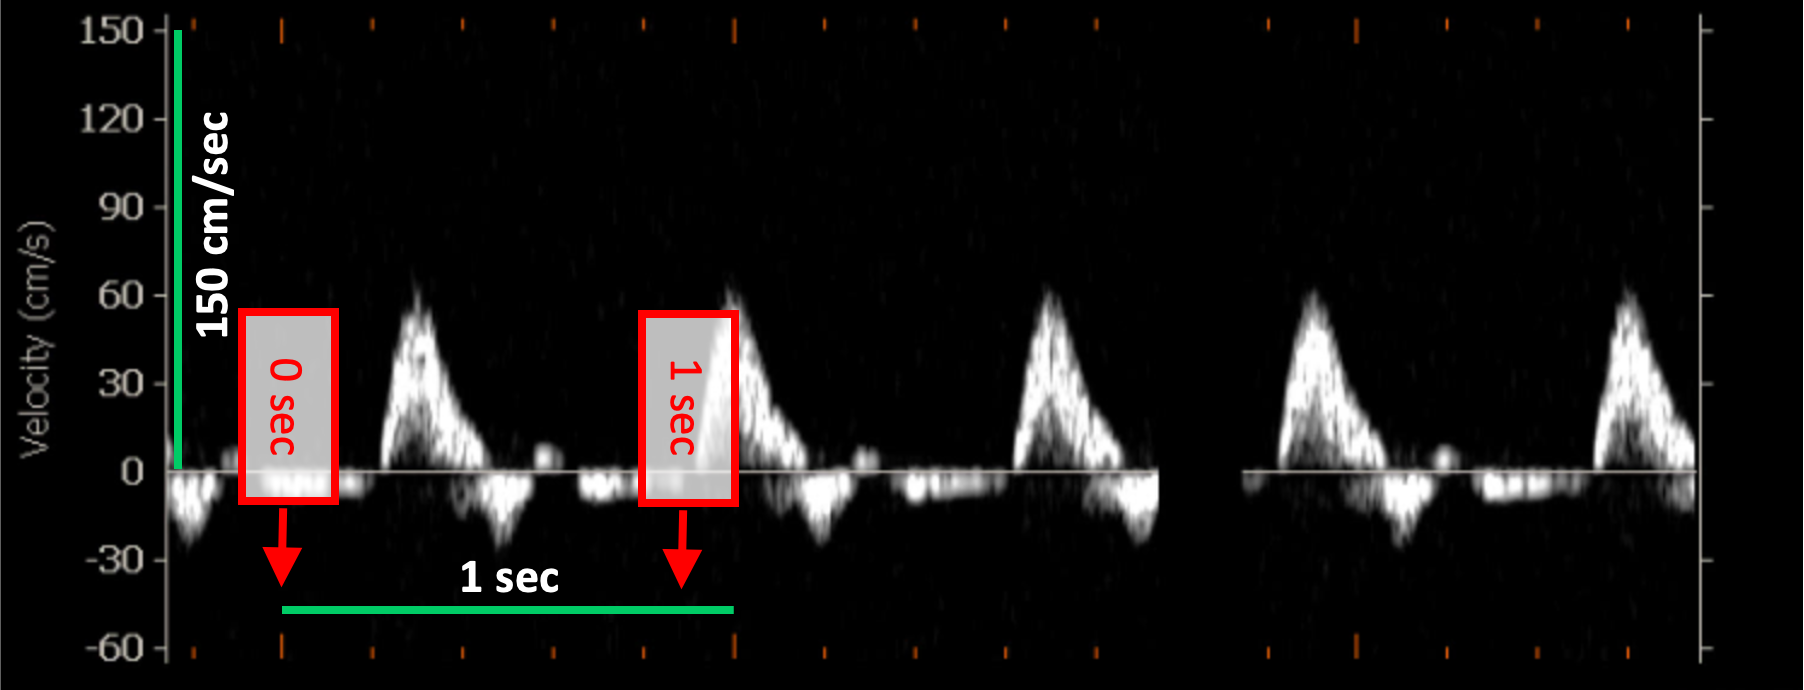

Exemples d'étalonnage de la vitesse Doppler

Les images suivantes présentent des exemples d'étalonnage de l'image Doppler de vitesse. Les éléments graphiques en rouge indiquent où trouver les informations relatives à l'échelle de temps dans l'image ultrasonore.